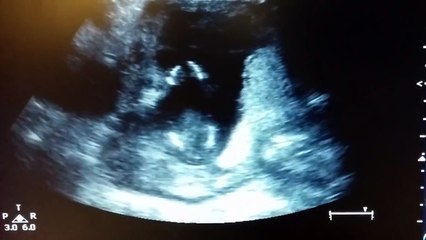

a 7 mois et demi de grossesse mon fils remue pas mal ds mon ventre! j'avoue ca fait trés bizart!